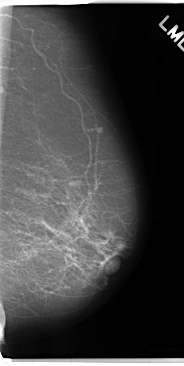

C_0181_1.LEFT_MLO

LEFT_MLO LINES 4752 PIXELS_PER_LINE 2392 BITS_PER_PIXEL 12 RESOLUTION 50 NON_OVERLAY